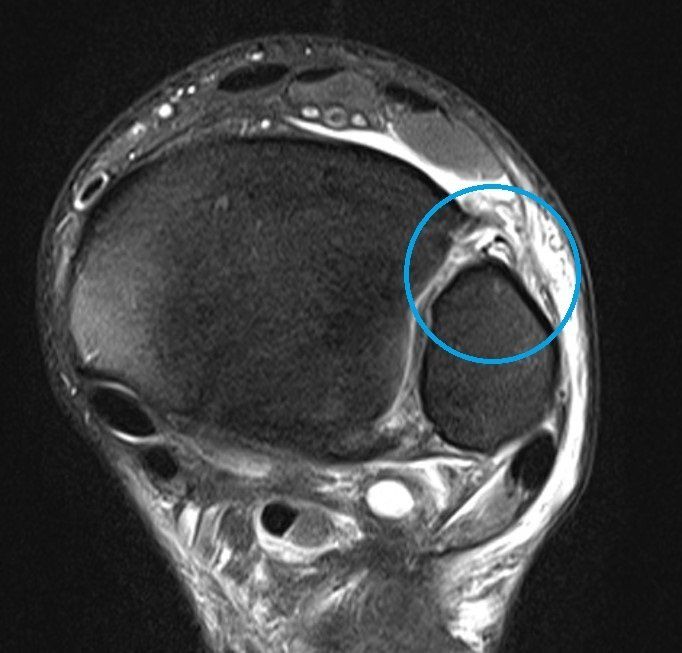

Weight-bearing X-rays comparing both ankles are useful, with MRI, weight-bearing CT and even ankle arthroscopy sometimes required to determine whether the syndesmosis is stable or unstable (see images below).